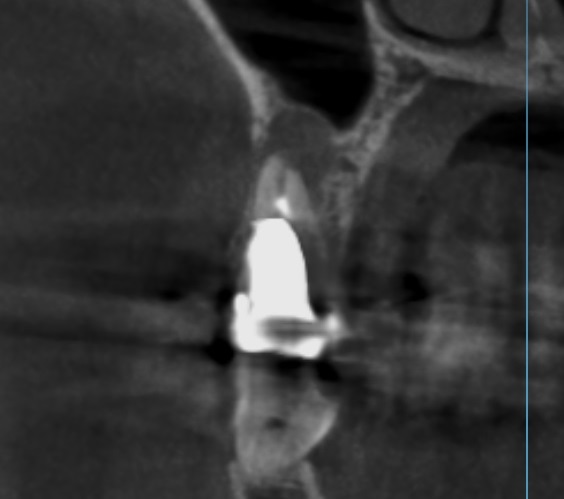

メタルコアCT画像

CT撮影で見るとこのような状態です。

メタルコア先の膿

そして根の先には膿が溜まっている像が認められます。(赤枠)

根の先の膿の治療をするには、根管治療が必要となります。

根管治療をするためにはメタルコアを外さなければなりません。